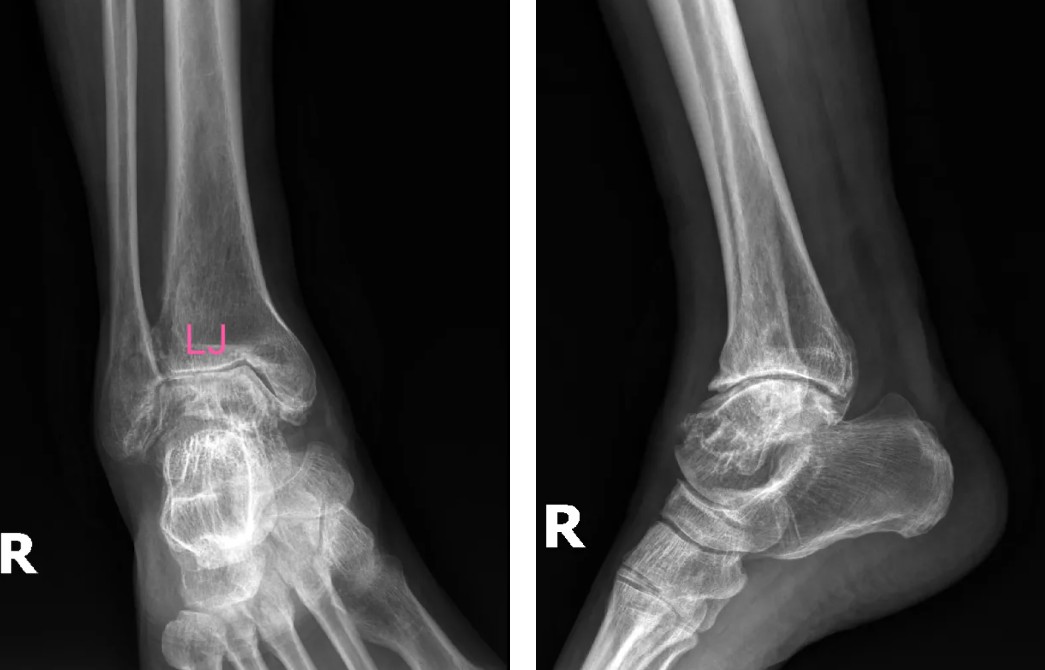

術(shù)前影像

患者吳先生(66歲)雙踝關(guān)節(jié)疼痛、活動受限長達10余年,保守治療無效后,關(guān)節(jié)逐漸畸形腫脹,連正常走路都成了奢望。廣安醫(yī)院副院長、關(guān)節(jié)科主任羅軍副主任醫(yī)師團隊經(jīng)全面評估,決定采用3D打印定制化人工全踝關(guān)節(jié)置換術(shù)。